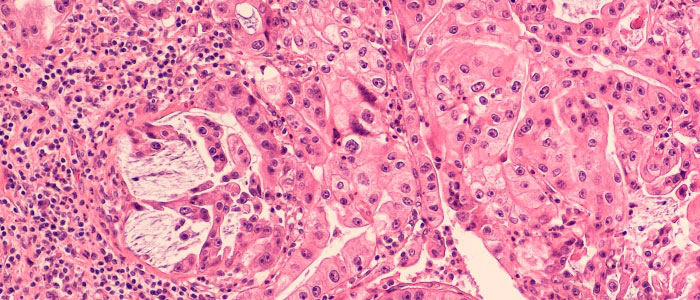

Scientists break new ground in potential treatment of common form of leukaemia

Glasgow researchers identify way to overcome chemotherapy-resistant leukaemia